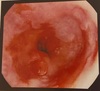

Q

a Lesão epitelial em epidermólise bolhosa.

b Esofagograma com estenose em epidermólise bolhosa. c e d Endoscopia com estenose de esôfago em epidermólise bolhosa